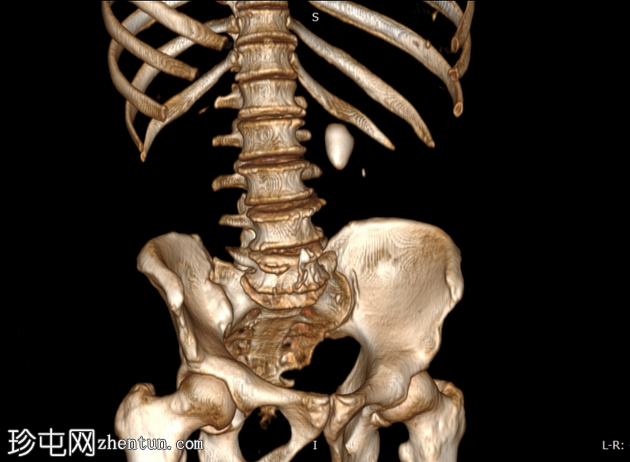

三维

重建

三维重建图像更清晰地显示了钙化结石;然而,需警惕腹主动脉钙化。

测量结石密度是CT检查在治疗方案制定中的主要原则。

对于我们的患者,肾盂结石密度大于1000亨氏单位(HU)适合采用体外冲击波碎石术。相反,密度小于 1000 HU 的肾下极结石或肾盂结石是经皮肾镜取石术 (PCNL) 的候选对象。